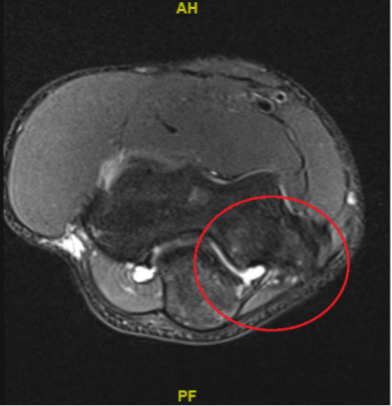

A 15-year-old right-handed male high school catcher presented to physical therapy with an approximate six-month history of medial elbow pain of gradual onset, having had an MRI with contrast (Figure 1). The accompanying radiologic report confirmed no presence of osteochondral lesion, fracture, or compromise of the anterior band of the ulnar collateral ligament. The report noted “marrow edema pattern of the distal humerus, medial epicondyle, olecranon, and proximal ulna involving the sublime tubercle and coronoid process most consistent with stress reaction in the setting of valgus extension overload.”